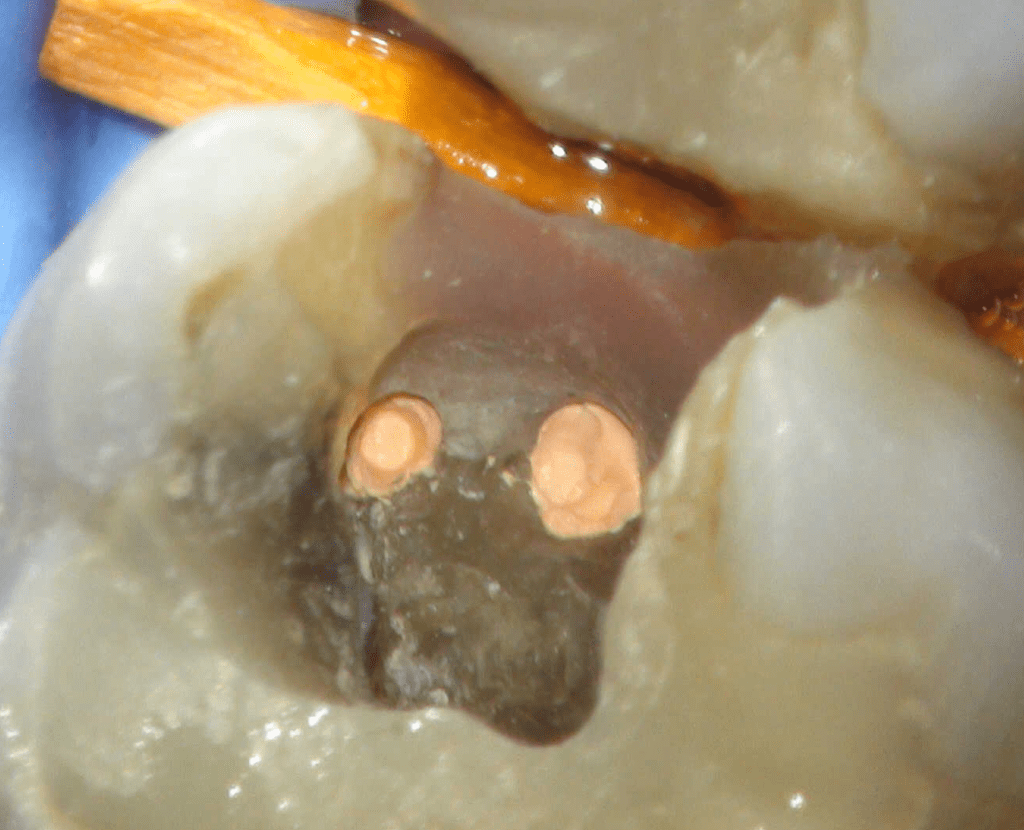

Reco preendo + 4 conductos molar superior

Reco preendo, 2o Molar superior